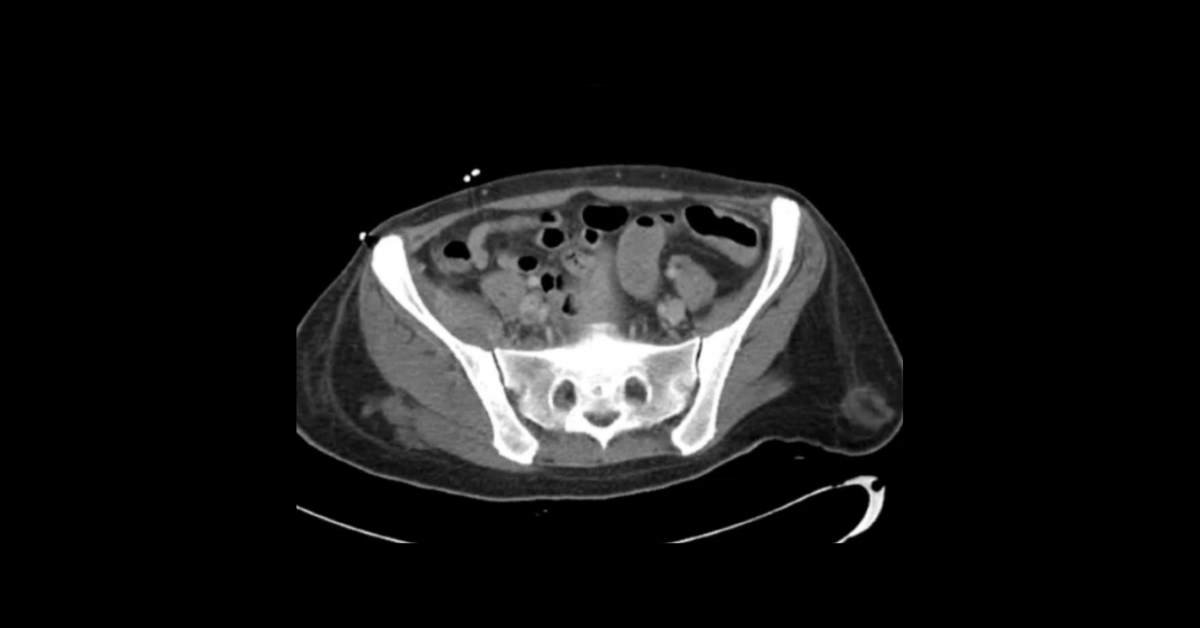

Presented by Vincent Mellnick, MD at Practical Radiology 2025. The upper gastrointestinal tract can be oft-overlooked site of disease in the emergency department patient, but is frequently be the site of pathology, including inflammation/infection, ischemia, obstruction, perforation, and hemorrhage. This talk will discuss common (and some uncommon) conditions causing these presentations in the esophagus, stomach, and duodenum, with emphasis on CT findings.